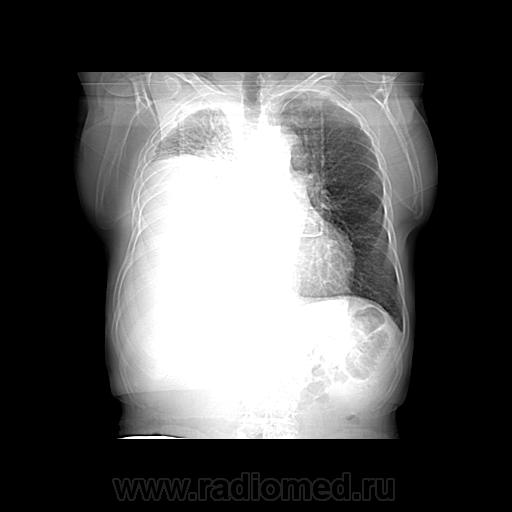

Пожилой мужчина, лечился по н/д правостороннней пневмонии в терап/отделении. Жалобы на одышку, кашель. По результатам Р-контроля после лечения направлен на КТ легких с диагнозом: плеврит справа, распад? В корне правого легкого вижу объёмное образование, с распадом. Смущают размеры плеврита,очень много жидкости, почти до 3 ребра. Анализы крови спокойные- L4,0-6,6, СОЭ 12-16мм. Неужто ТБС, отсев бы был при таком огромном поражении. В посеве мокроты-100% высев клебсиэллы пневмоние. Мокрота на общий анализ в работе-собирает с трудом, изза отсутствия мокроты. Плевральную пункцию еще не проводили. Н азначила бронхоскопию и плеврал пункцию. Как думаете, уважаемые коллеги, это онкопроцесс или тбс распад?

Не смотря дайкомы, только по рентгенограмме, предположил бы центральный рак правого легкого. Потому что большой гидроторакс, без смещения средостения в здоровую сторону, как правило, соответствует раковому ателектазу.

Небольшое количество увеличенных лимфоузлов, и те - не сказать, чтоб были очень крупными. От эмпиемы до онкологии... Умеренное количество жидкости в перикарде, толщиной слоя до 13-14 мм. При подобной картине не вижу смысла гадать по сжатому лёгкому, пишу так: массивный выпот справа, около 2500 мл, диафрагма оттеснена жидкостью каудально, печень (!!!) смещена каудально и вправо. Легкое справа значительно компрессировано жидкостью, оценка проходимости бронхов и состояния легочной паренхимы (кроме имеющейся эмфиземы) практически невозможна. Необходима пункция плевральной полости справа (цитология, ВК, посев на микрофлору и проч), КТ-контроль после эвакуации жидкости.